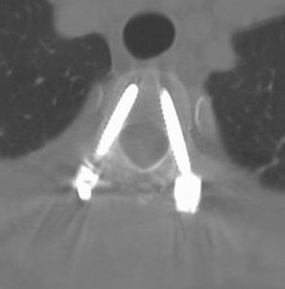

頚椎前方固定術はその侵入経路より、あまり長い範囲の固定には適しません。後方固定術にはそのような制限はなく、理論的には脊椎すべてを処置することも可能です。関節リウマチや腫瘍性疾患、特殊な変性疾患など、長い範囲で脊椎の安定化、固定が必要な時に実施します。ただ、頚椎というその他の部位の脊椎よりも「骨のサイズが小さく」、「構造的に複雑な骨」に対して、スクリューなどの固定具を挿入するため、難易度が高く、患者さまもそれらのリスクを十分に理解された上で手術を受けられることが望ましいと考えます。

![]() 頚椎後方固定術術後CTC3 |